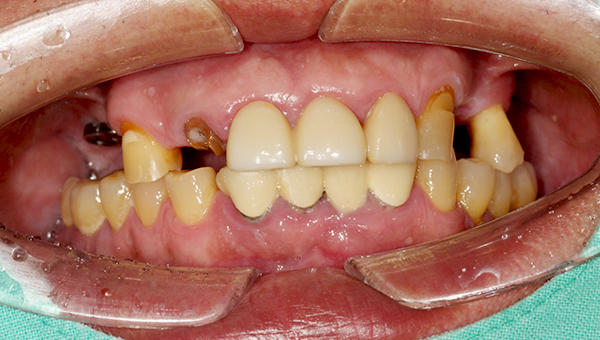

심*복 임플란트 시술 사례

전체 임플란트

2024.12.05

치료 전

2025.05.30

치료 후